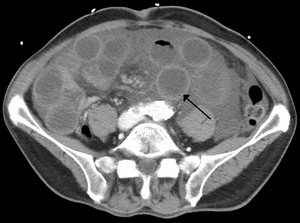

| Computer tomography (CT) showing dilated loops of small bowel with thickened walls (black arrow), findings characteristic of ischemic bowel due to thrombosis of the superior mesenteric vein. | |